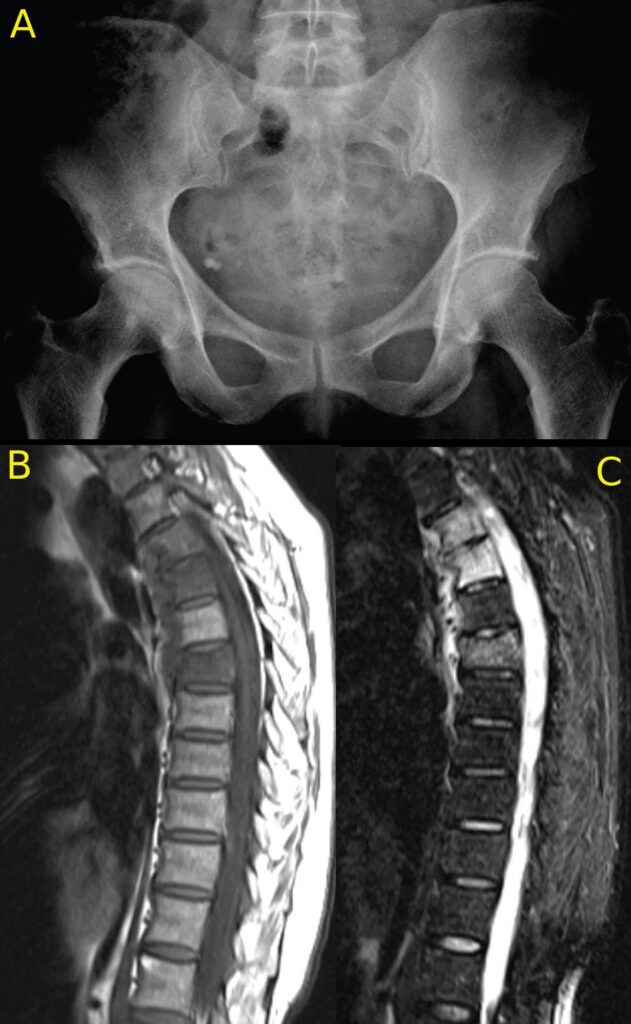

From radiologykey.com

Psoriatic Arthritis Radiology Key Psoriatic Arthritis In Upper Back People who are ultimately diagnosed with psa can look back and identify symptoms that occurred for months and years beforehand. The two types of pain will feel different and are accompanied by different symptoms. Inflammatory back pain from psoriatic arthritis has the following characteristics: When you think of psoriatic arthritis (psa), you may imagine skin symptoms or the commonly affected. Psoriatic Arthritis In Upper Back.

From www.the-rheumatologist.org

Imaging of Axial Psoriatic Arthritis The Rheumatologist Psoriatic Arthritis In Upper Back I was cleared to restart yesterday. Begins before you’re 35 years old. Back pain caused by psoriatic arthritis can be inflammatory, which has an unknown onset, or mechanical, which is caused by an injury. The two types of pain will feel different and are accompanied by different symptoms. People who are ultimately diagnosed with psa can look back and identify. Psoriatic Arthritis In Upper Back.

Psoriatic Arthritis Radiology Key Psoriatic Arthritis In Upper Back I’m used to (and am. Persists for at least three months and can gradually worsen over many years. When you think of psoriatic arthritis (psa), you may imagine skin symptoms or the commonly affected joints, like the fingers, knees, ankles or elbows (peripheral arthritis). Here is a look at three general phases of psoriatic arthritis and what each one is. Psoriatic Arthritis In Upper Back.